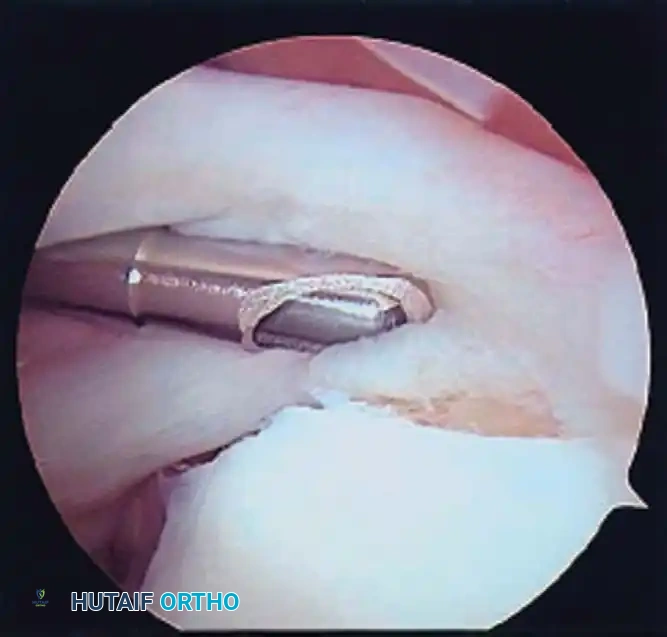

Electrocautery and Radiofrequency Ablation

In addition to hydrostatic pressure, active hemostasis is achieved using arthroscopic electrocautery or bipolar radiofrequency (RF) ablation devices. These wands are indispensable for coagulating bleeding vessels in the subacromial bursa, releasing the coracoacromial ligament, and meticulously preparing the footprint for rotator cuff repair without obscuring the visual field with hemorrhage.

Furthermore, the addition of epinephrine (typically 1 mg per 3 liters of irrigation fluid) induces local vasoconstriction, significantly reducing capillary oozing. When combined with controlled hypotensive anesthesia (maintaining mean arterial pressure between 70-80 mm Hg), the surgeon is afforded a pristine, bloodless field, allowing for the precise execution of complex knot-tying and tissue mobilization.